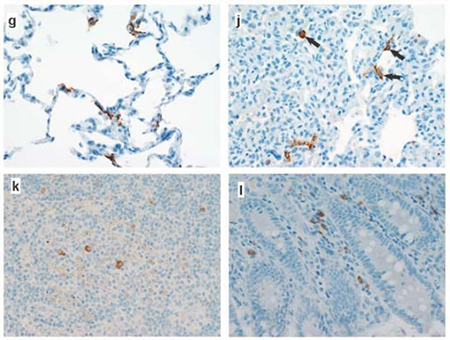

感染 SARS-CoV-2 的恒河猴的病理变化。通过免疫组化检测以下细胞/组织中的 SARS-CoV-2 核衣壳抗原:(g)Ⅰ 型肺泡细胞;(j)Ⅰ 型肺泡细胞,Ⅱ 型肺泡细胞及肺泡巨噬细胞;(k)纵隔淋巴结和(l)盲肠固有层中的巨噬细胞和淋巴细胞。图片由 bioRxiv March 21, 2020// doi. org/ 10. 1101/ 2020. 03. 21. 001628 一文 Figure 4 修改。